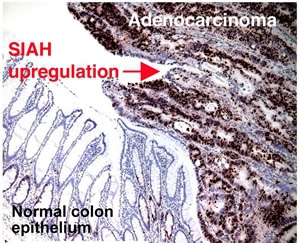

SIAH2